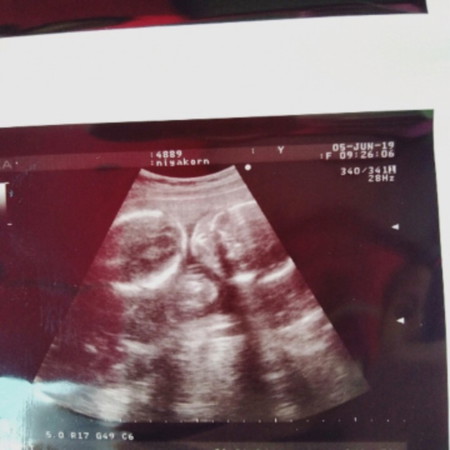

บ้านนี้ แฝด ผู้หญิงกับผู้หญิง 25+5 วีค

บ้านนี้แฝดชายค่ะ 21+1วีค